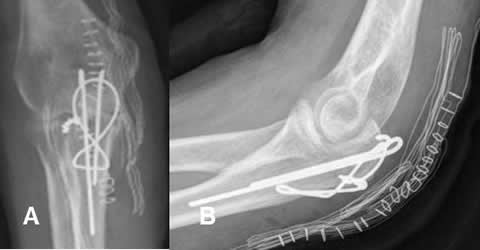

Fig 104. Grapas.

A y B: Rx AP. Grapas utilizadas para fijar el injerto del LCA.

En B se aprecia tornillo ubicado sobre el túnel femoral, que fija el injerto proximalmente.